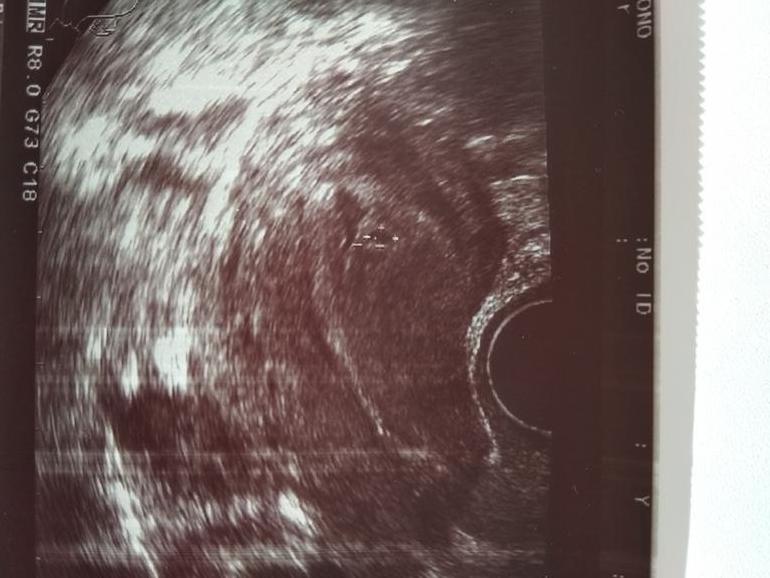

вот еле видное маленькое плодное яйцо.

У меня последние М были 18 января при том они у меня не регулярные,овуляция не знаю когда была,но на прошлые беременности мне всегда ставили позднюю овуляцию,а тут на УЗИ сказали для такой задержки маленькое плодное яйцо ,тест показал еле слабую полоску на 41 день цикла и за 10 дней тестик стали хорошими.

Мне в 5,2 поставили неразвивающуюся беременность пя 10мм. А в 6,1 уже эмбрион был 4,3 мм и сердцебиение. Через недельку сходите